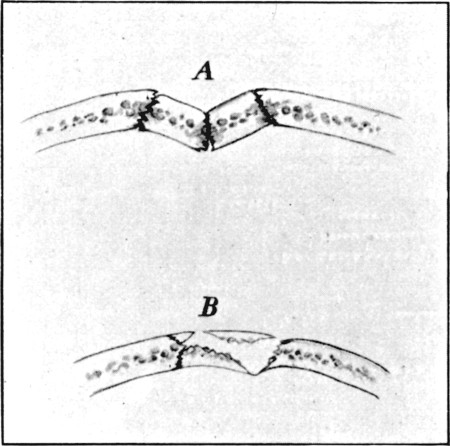

1. Section of Mauser Aperture of Entry To face p. 73

2. Section of Mauser Aperture of Exit 76

25a. Sections of Mauser Entry and Exit Wounds74

61. Diagram of Aperture of Entry into Cranium 245